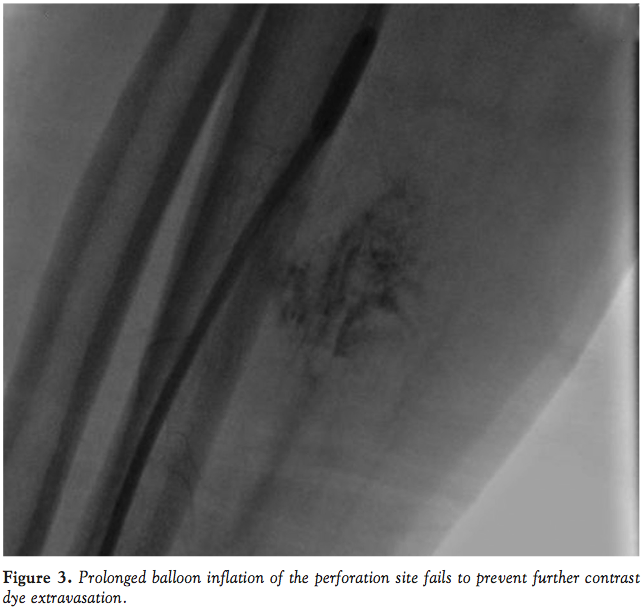

The patient developed pain in the volar aspect of his right arm soon after the guiding catheter was advanced over the J-tip wire. Progressive expansion of a hematoma was noted, and after successful PCI, a peripheral angiogram was performed of the right radial artery, demonstrating a perforation with persistent contrast dye extravasation and soft tissue staining (Figure 2). The bivalirudin infusion was immediately stopped and prolonged balloon inflation using a semi-compliant coronary balloon (Trek, 4.00 mm diameter, 15 mm length;

Abbott Vascular) was undertaken at 8 atm of pressure for 500 seconds (Figure 3). Despite these measures, persistent extravasation of dye was noted, along with arm pain and hematoma expansion. A coronary polytetrafluoroethylene (PTFE)-covered stent graft (JoStent Graftmaster, 4.00 mm diameter, 19 mm length; Abbott Vascular) was placed at the site of the radial artery perforation to obtain hemostasis (Figure 4). Following successful deployment of the covered stent graft at the site of the radial artery perforation, no extravasation of contrast dye was noted. The patient was admitted to the coronary care unit and monitored for the development of compartment syndrome. At 2 week follow-up, the hematoma had resolved.